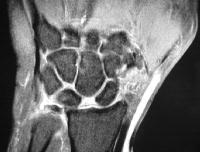

Case 1. Chronic complete scapholunate ligament disruption seen on MRI

Click for larger image

Palmar flexion of the scaphoid, lunate dorsiflexion.

Scapholunate diastasis.